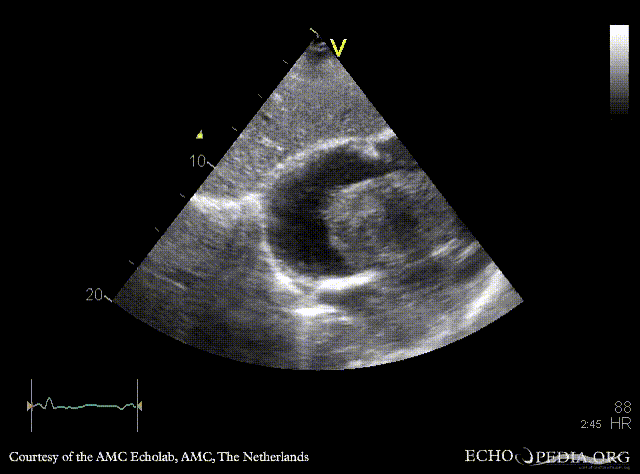

| Giant myxoma in right atrium

| PSAX

A4CH